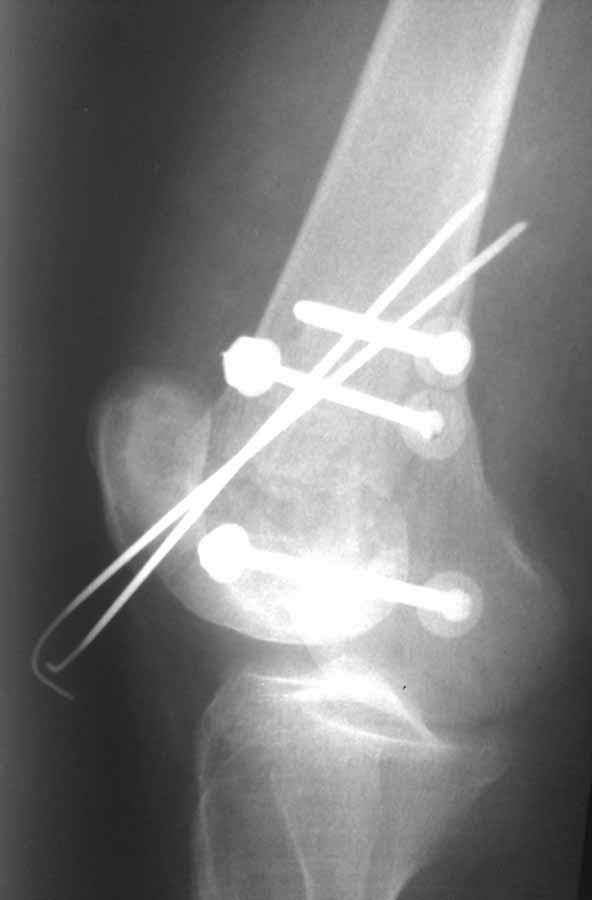

Коллеги, извиняюсь за задержку с результатом. Через медиальную артротомию обнажили н/3 бедра, отрепонировали внутренний мыщелок, затем по нему сопоставили суставную поверхность бедра с латеральным мыщелком.

Больная выписана в ортезе с регулируемым углом сгибания в колене, с рекомендациями через 3 нед. удалить спицы и начать разрабатывать сустав.